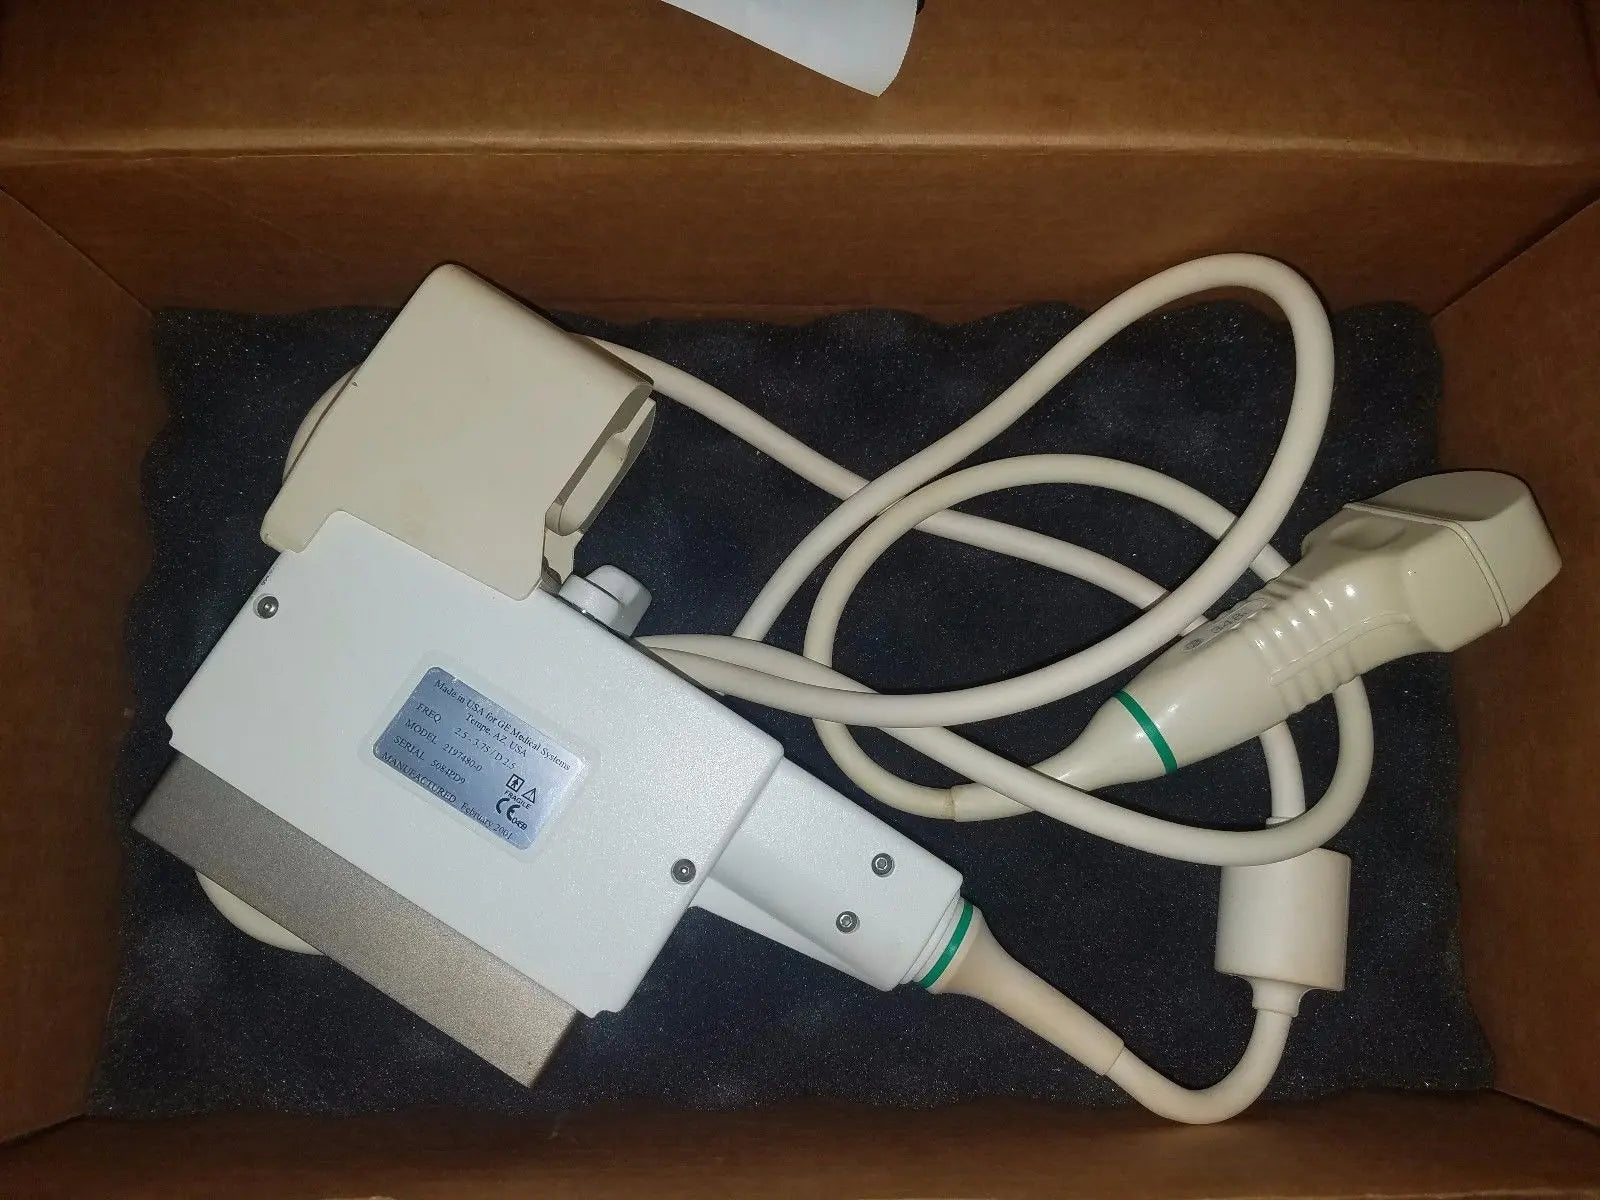

DIAGNOSTIC ULTRASOUND MACHINES FOR SALE

GE 348c Ultrasound convex ultrasound transducer

Sale price$ 1,439.90

DIAGNOSTIC ULTRASOUND MACHINES FOR SALE

GE 348C 2197480 ULTRASOUND TRANSDUCER PROBE

Sale price$ 3,599.78